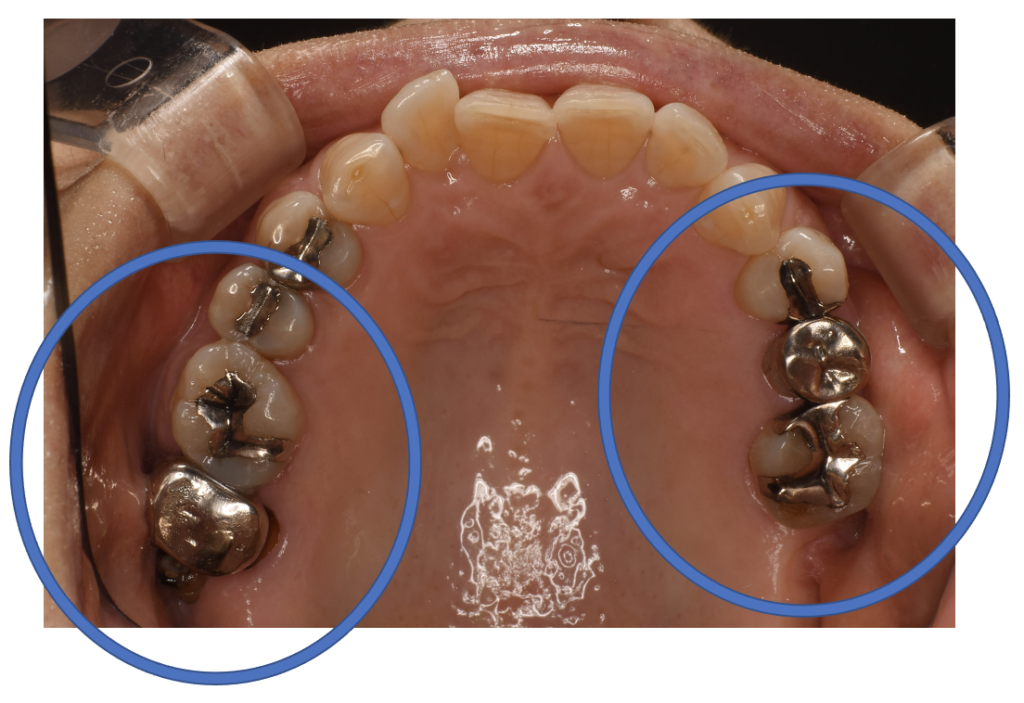

フルジルコニアCr 17 No.42

Before

| 治療方法 | フルジルコニアCr 虫歯などで失った歯質を天然歯と同じ色・質感のセラミックの一種であるジルコニア(人工ダイヤモンド)で補う治療法。 |

| 治療のデメリット | 変色がなく耐久性の高い治療ですが、歯周病や二次虫歯を予防するためには歯科医院での定期的なメインテナンスが大切です。 |

| 費用 | ¥89,000×2本=¥178,000 |

| 通院回数 | 1ヶ月〜6ヶ月 |

| 備考 | 院長より 銀の詰め物の内部に虫歯が進行してしまっていたケースです。中を開けて見てみると、外から想像するよりもはるかに虫歯が広がってしまっていました。幸運にも神経を保存できたので、生きた臓器としてまだ使うことが可能です。残存歯質がかなり薄く弱くなってしまったので、ジルコニアで2本を被せて守ってあげています。一番奥の銀歯は内部で虫歯が進行しすぎてて、折れてしまっていて、残念ながら抜歯を しなくてはならない状況でした。 |